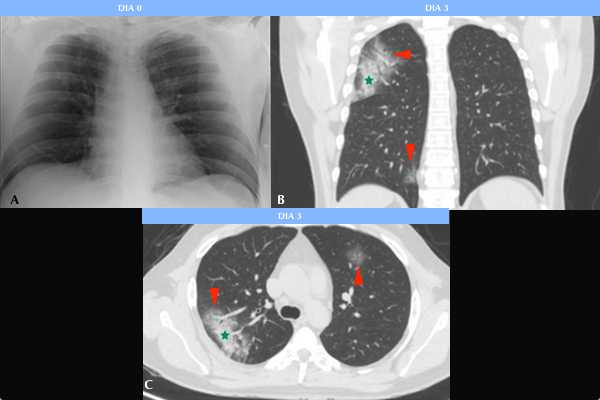

De los 11 pacientes COVID-19 positivos con hallazgos patológicos en la Rx, 8 (72%) se manifestaron como opacidades parcheadas en vidrio esmerilado y 3 (27%) como una asociación de infiltrados en vidrio esmerilado y consolidaciones (Fig. 1). En 8 (72%) pacientes las opacidades se distribuyeron en los lóbulos inferiores, dentro de los cuales 3 (27%) de ellos también mostraron compromiso del lóbulo medio. Solo 3 (27%) pacientes presentaron afectación. Se menciona además compromiso bilateral en 7 (63%) pacientes y unilateral en los restantes 4 (36%).

Se pudo estudiar la evolución radiológica de esta enfermedad en uno de los pacientes cuya evolución clínica fue tórpida, observándose en una radiografía inicial sutiles áreas parcheadas en vidrio esmerilado en campos pulmonares inferiores, las cuales fueron progresando hasta volverse coalescentes, difusas y consolidativas, llegando a afectar la mayor parte del parénquima pulmonar, asociándose además a derrame pleural. El paciente requirió intubación orotraqueal al décimo día de internación, sin lograr mejorar su cuadro clínico, y se constató su deceso 10 días más tarde (Fig. 2).